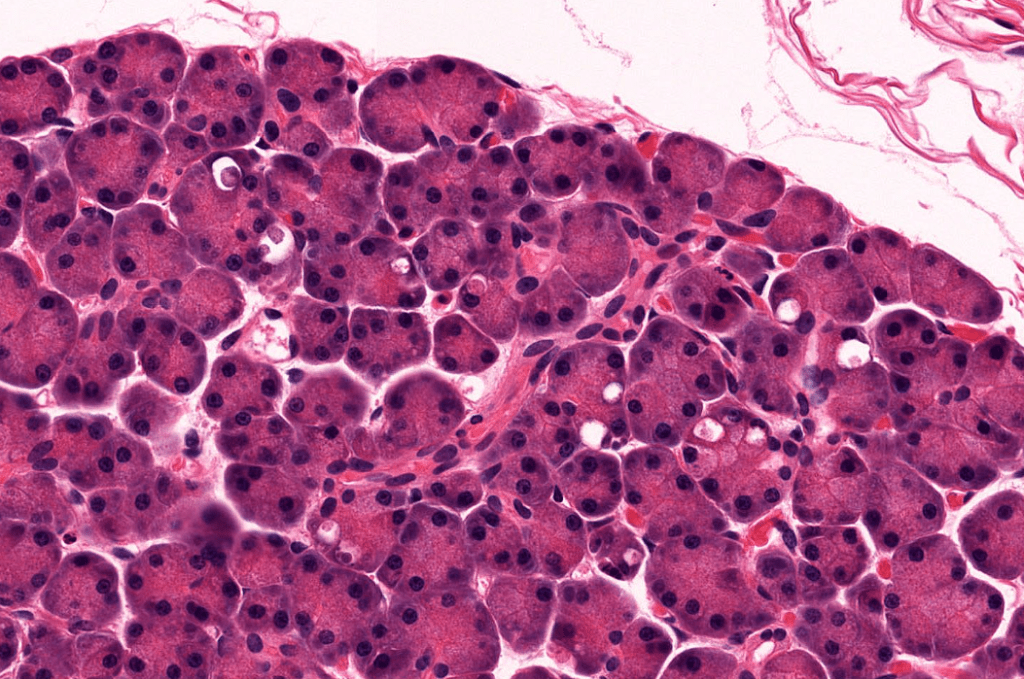

ACINOS SEROSOS EN PÁNCREAS

Conforman la parte exocrina del páncreas, su función principal es la secreción de zimógenos.